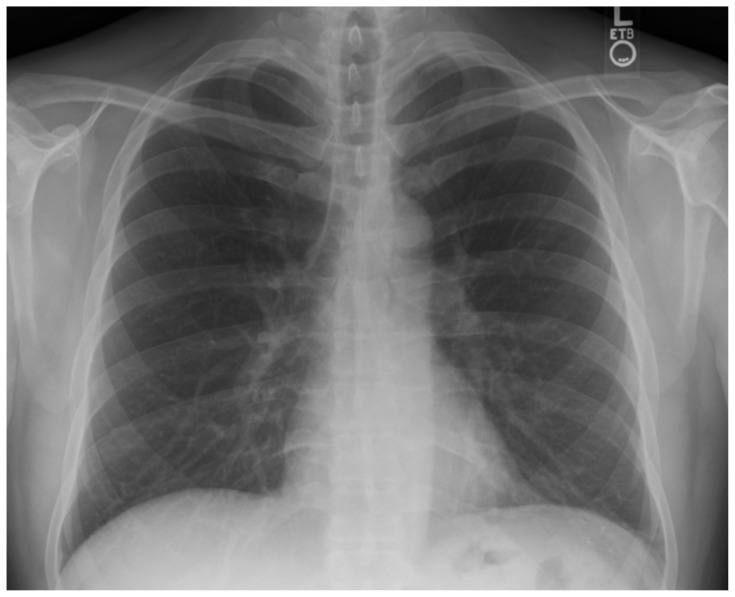

| #8 | Chest X-ray |

Chest X-ray

Gaillard F. Normal chest x-ray. In: Radiopaedia. Accessed March 25, 2023. CC BY-NC-SA 3.0 At: https://doi.org/10.53347/rID-8304